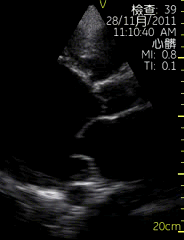

胸骨旁左室长轴切面

| 图像名称: | 胸骨旁左室长轴切面(二维) |

| 胸骨旁左室长轴切面(二维) | | 介绍重点: | 长轴切面心肌收缩有力、二尖瓣前后叶呈镜向运动 |

| 室间隔回声中断,可见明显缺口,左室增大 |

| 左房、左室增大,室壁运动幅度降低;二尖瓣启闭受限; | | 临床用途: | 评估房室大小,心脏功能;(正常图像) |

| 室间隔缺损; |

| 左室收缩功能降低 |